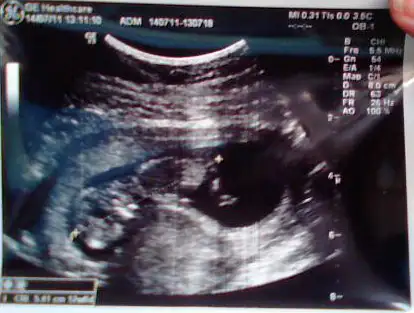

gülşah bebegin konumuna göre bebek kız

ama bazı kişilerin dedigine görede kese fasulye şeklindeyse bebek erkek,yuvarlaksa kız diyorlarrr

kızımınki hem yuvarlak hemde bebek sagda.

Kızlar eklediğim resim inşallah çıkar bende çok merak ediyorum bebeğim 11+3 günlük, inşallah bişiler yazarsınız... sevgiler hepinize...

kizin olacak sanirim yuvarlak olduguna gore hiiiiiEki Görüntüle 221294kızlar benim miniimide yorumlayın kızmı....